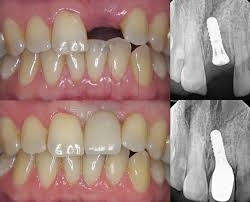

TOOTH REPLACEMENT